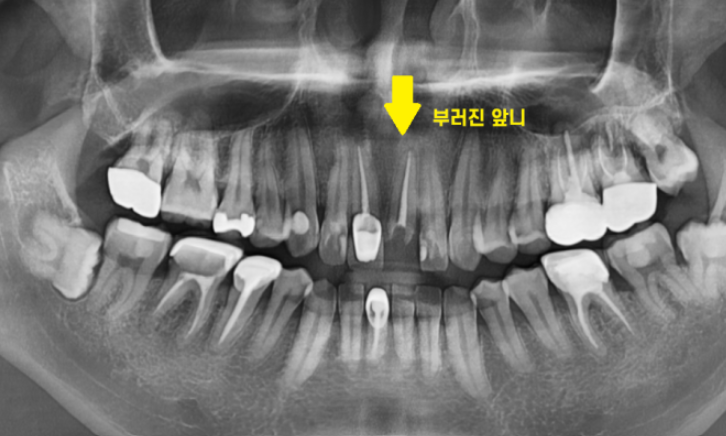

작은 x-ray로 한 번 더 확인해 보았습니다.

2/3 이상 머리가 없어졌네요..

앞니 부러짐 치료의 방향을 결정할 때에는

남아있는 치아의 양이 중요합니다.

살릴 수 있을지 없을지

예후를 결정하는

key point이죠!!

잇몸뼈에 뿌리만 박혀있는 수준이라

발치 후 임플란트 계획을

잡아드렸습니다.